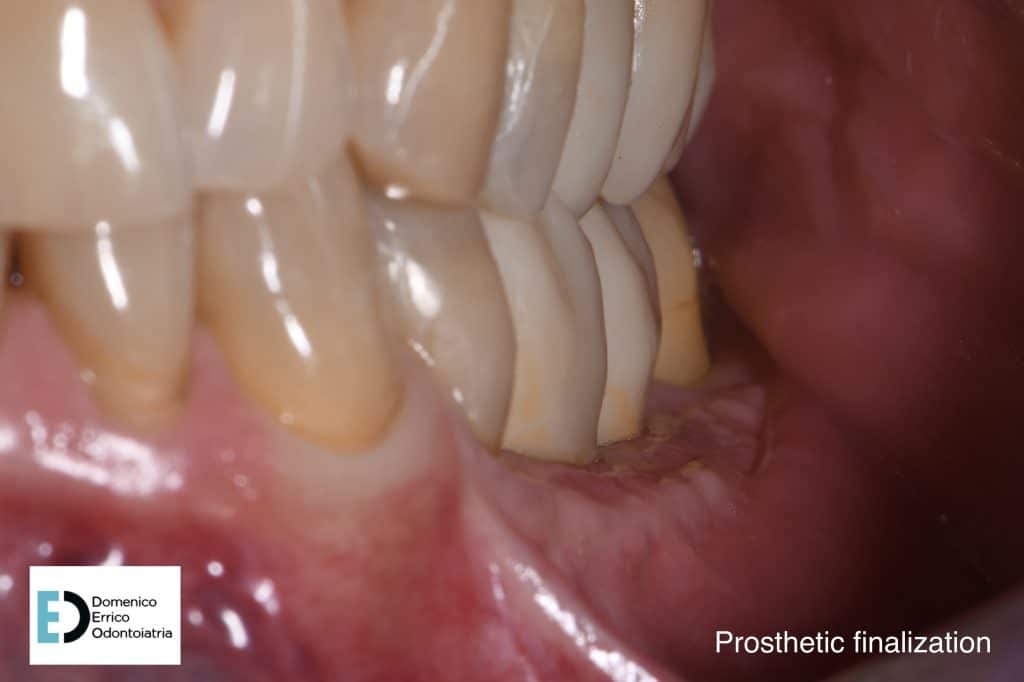

The treatment objectives are primarily functional: the restoration of volumes, necessary for implant rehabilitation due to insufficient bone height for fixture placement applying a mesh with a filler, consisting of 50% autologous bone and 50% heterologous bone; the reinstatement of chewing function by a second intervention to remove the mesh and simultaneously place two implant fixtures, concurrent with an increase of adherent gingival tissue level; and finally, the goal is to achieve the correct vertical relationship between the upper and lower arches through prosthetic rehabilitation of the upper arch with the replacement of the old prosthetic device.

After 4 months we can appreciate the perfect tissues healing, the bone level stability, a perfect implants osteointegration, with a complete recovery of masticatory function and an aesthetic balance between teeth and gum portions.